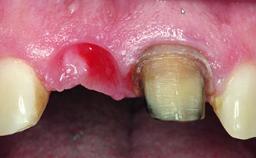

A 32-year-old female Caucasian patient with a compromised maxillary right central incisor was referred to us by a general dentist. Her chief complaints were discomfort and mobility of tooth 11 with unsatisfactory esthetics due to discoloration. The patient reported a previous trauma, some years earlier, as the origin of pathology on the afflicted tooth. Anamnesis was negative for any other dental or periodontal pathology in the remaining dentition. The patient did not take any medication and reported to be a light smoker (5–10 cigs/day). She had high esthetic expectations of her treatment. The extraoral examination revealed a high smile line with full exposure of her maxillary teeth and surrounding soft tissue in the area between the second premolars.

Soft Tissue Grafting Staged

Soft Tissue Contour and Volume Slightly compromised